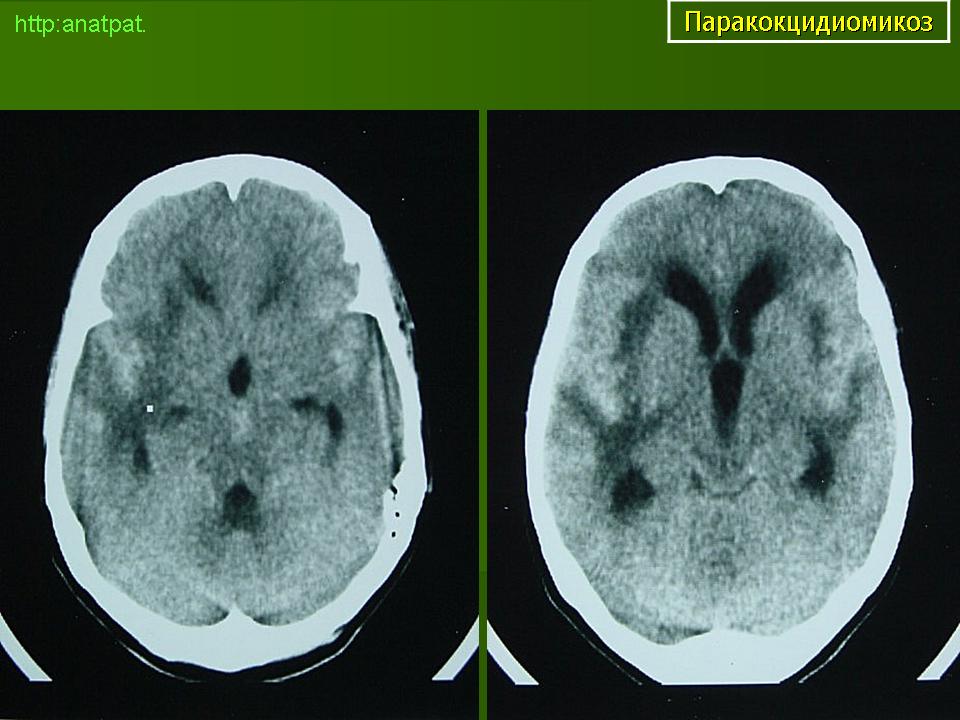

ГМ. Паракокцидиомикоз. +

Паракокцидиомикоз.

Множественные "узловые образования" имитирующие метастазы.